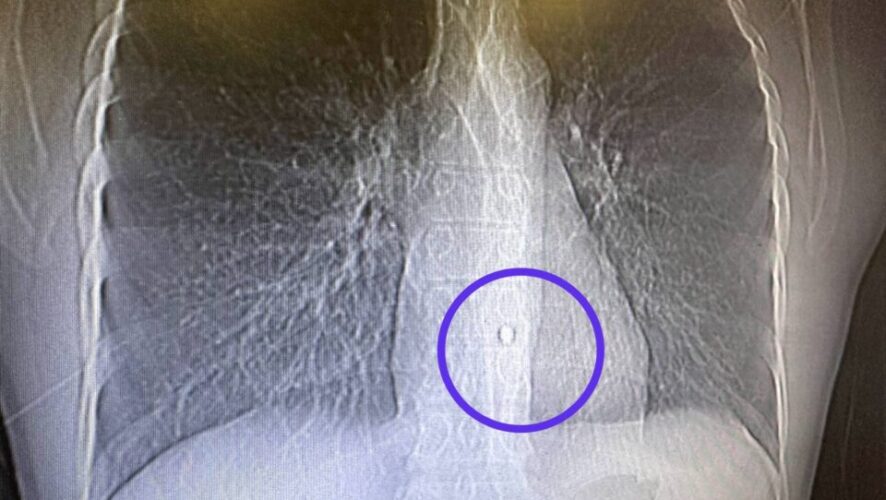

Врачи казанской РКБ достали осколок из аорты бойца СВО через проколы. Об этом сообщили в пресс-службе Республиканской клинической больницы Казани.

Так, 17 марта военнослужащий из Татарстана получил осколочное ранение левой половины грудной клетки с повреждением легкого, один из осколков попал в стенку аорты.

Команда торакальных хирургов и анестезиологов смогла извлечь осколок через проколы за 2,5 часа.